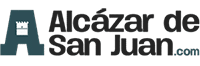

Ahora, una investigación realizada por expertos de varias instituciones alemanas y publicada esta semana en The Journal of Neuroscience sostiene que la representación de los genitales en el mapa cerebral está cerca de la representación de la cadera si bien hay que localizarlo individualmente ya que la ubicación precisa varía “probablemente” entre ellas.

“Nuestro enfoque de mapeo produjo activaciones corticales en la pared lateral de la corteza somatosensorial para todas las mujeres, aunque la localización precisa cambió de mujer a mujer”, explica a SINC Christine Heim, profesora de la Universidad Charité de Berlín (Alemania) y autora principal.

Los estudios anteriores arrojaron resultados contradictorios debido a los métodos de mapeo menos precisos. En esta ocasión, el equipo utilizó la imagen por resonancia magnética funcional para cartografiar la representación exacta de los genitales femeninos midiendo la respuesta del cerebro a una membrana que vibraba sobre la región del clítoris.

“Nuestro enfoque de mapeo individual proporcionó una mayor precisión que en investigaciones anteriores y localizó inequívocamente el campo genital”, continúa Heim, que recogió una muestra de 20 mujeres.

Variabilidad interindividual de la corteza somatosensorial genital. / Knop et al., JNeurosci 2021